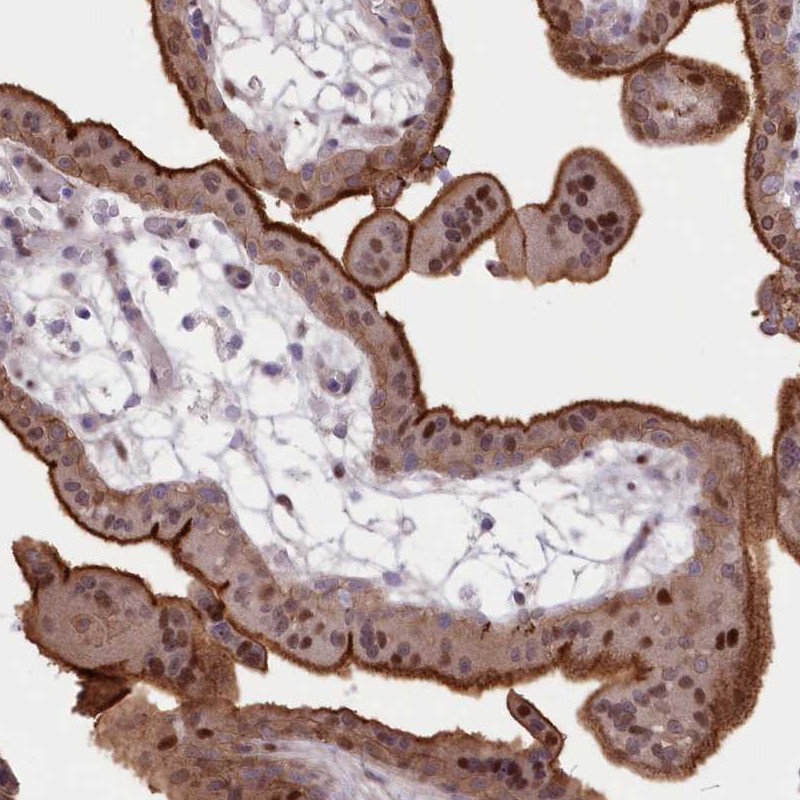

Immunohistochemical staining of human placenta shows strong membranous and moderate nuclear positivity in trophoblastic cells.